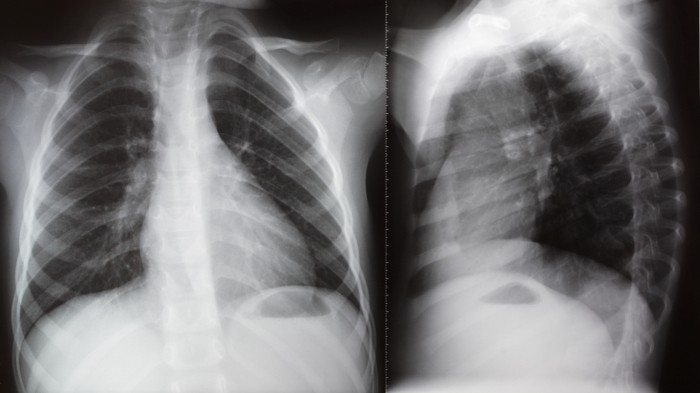

이번 ‘동종 제대혈 유래 중간엽 줄기세포 성분(주사제)’은 메디포스트가 임상시험 중인 ‘뉴모스템®(PNEUMOSTEM)’으로, 최근 식약처로부터 개발 단계 희귀의약품 지정 고시 예정 통보를 받았다. 기관지폐이형성증은 미숙아의 사망과 합병증 발생의 가장 중요한 원인이 되는 질환으로 매년 2천여 명의 환자가 발생하고 있으나, 현재까지 뚜렷한 치료 방법이나 허가 받은 치료제가 없는 실정이다. 메디포스트는 제대혈(탯줄 혈액)에서 추출한 중간엽줄기세포를 원료로 이 같은 질환의 예방 치료제를 개발, 현재 삼성서울병원과 서울아산병원에서 제 2상 임상시험을 진행 중이다.